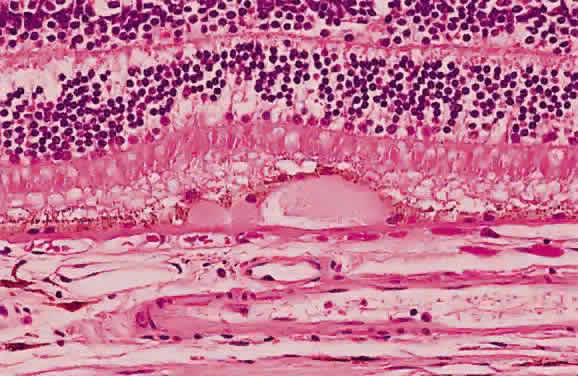

Fibrous tissue may originate from the choroid and proliferate through breaks in Bruch's membrane into the subpigment epithelial or subretinal spaces,4 hence the white appearance of disciform macular degeneration (Fig. 16). Fibrous tissue also may originate from fibroblasts located in the adventitia of retinal vessels and may contribute to the white appearance of vascularized membranes (Fig. 17A), such as those seen in proliferative diabetic retinopathy (see Fig. 17B) or arterioles after vascular occlusion (see Fig. 6). The accretion of collagen in the wall of the vessel in arteriolosclerosis may thicken the vessel wall (see Fig. 5) and alter the color of the blood column to a copper or silver color. Injury to the pigment epithelium results in scar formation (Fig. 18). Collagen deposition from pigment epithelium metaplasia may be identified by the presence of pigment within a scar (Fig. 19). Injured nonpigmented epithelium may undergo similar fibrous metaplasia and may contribute to the formation of membranes such as cyclitic membranes in the region of the ciliary body.

Fig. 19. Histologic section demonstrating response of the pigment epithelium to injury. The sclera is at the bottom the micrograph; the choroid (c) contains scattered red blood cells and is edematous. The vitreous (v) also contains hemorrhage. Locate the pigment epithelium (short arrows) at the left third of the micrograph and notice the ribbons of pigment epithelium that proliferate into the membrane, partially formed by fibrous tissue (F). Bone (long arrow) also is present and probably was deposited by metaplastic pigment epithelium.